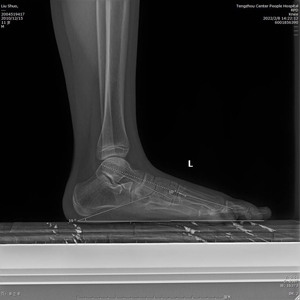

術(shù)前X線示:左足平足并副舟骨。患者經(jīng)過足跟墊等保守治療效果不佳,潘維亮主任醫(yī)師主持全科醫(yī)護人員術(shù)前討論一致決定為患者實施全麻下距下關(guān)節(jié)制動術(shù)。

(術(shù)后X線)